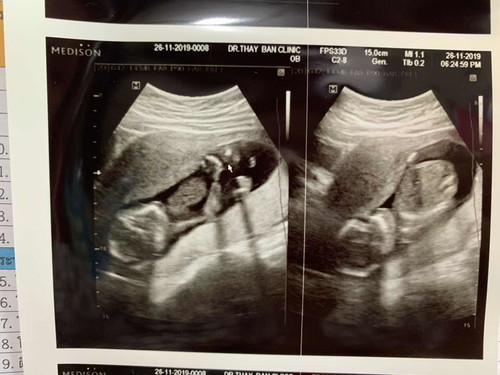

อันนี้ตอน 12 วีคค่ะ น้องเอาหัวทิ่มลงพื้นอย่างที่เห็นเลยจ้า จนหมอวัดความยาวน้องไม่ได้เลย แต่ไม่ได้อันตรายนะคะ เค้าจะหมุนได้360องศาแล้วแต่อารมณ์เค้าเลย